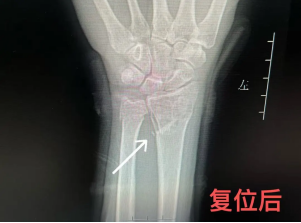

尺桡骨骨折主要治疗方式包括:手法复位,手术切开复位,内、外固定等治疗

复位后,必须立即进行拍片,从影像上确认骨折对位对线是否良好